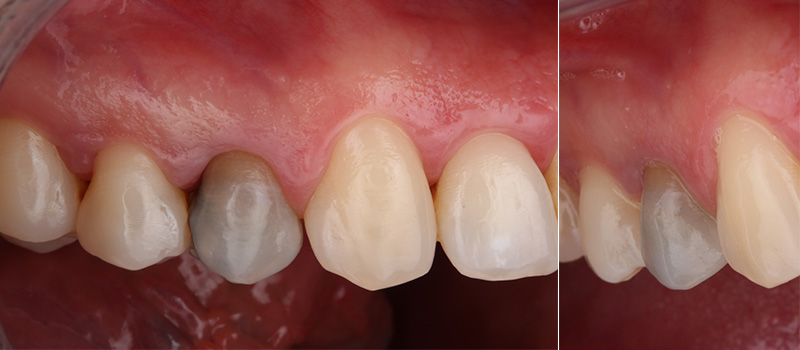

Fig. 05 : situation clinique à J10 (avant la dépose de la suture en 6.0 monofilament) vue latérale et vue vestibulaire.

Fig. 06 : situation clinique à 4 mois de cicatrisation vue vestibulaire et vue latérale.

Fig. 11a & 11b : contrôle clinique à 3 ans post-opératoire vue vestibulaire et vue latérale.